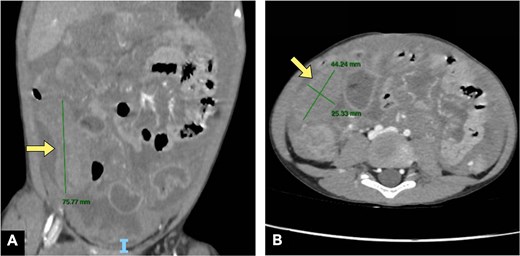

The complete blood count showed a WBC 32 × 109/L (neutrophils 88.91%), serum K+ 7.87 mmol/L, and a normal creatinine (71 μmol/L), suggesting that the hyperkalemia was not caused by acute kidney injury (AKI), which would be the typical cause in a septic patient. An abdominopelvic computed tomography (CT) scan with contrast showed a 7.5 × 4.5 × 2.5 cm solid mass in the right iliac fossa with large ascites (Fig. 1). Severe hyperkalemia, absence of AKI, along with marked leukocytosis and an abdominal solid mass, supported the initial suspicion of an aggressive malignancy. Tumor lysis syndrome (TLS) laboratory tests showed hyperuricemia (of 542 μmol/L) and a normal level of phosphorus (1.28 mmol/L). We suspected perforated appendicitis with underlying malignant etiology leading to severe systemic sepsis and TLS.

Abdominal CT in the (A) coronal plane and (B) axial plane demonstrates a dilated appendix (yellow arrows) with a moderate amount of peritoneal fluid.